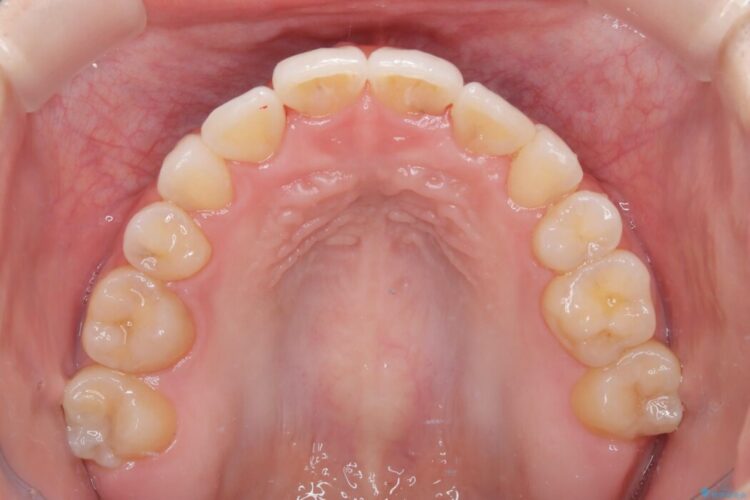

上顎は二重歯列で前歯のがたがた(叢生)が強いため、抜歯を行う治療計画を立てました。

叢生の度合いも強く、3年と治療期間はかかりましたが患者さんにも非常に満足していただけました。